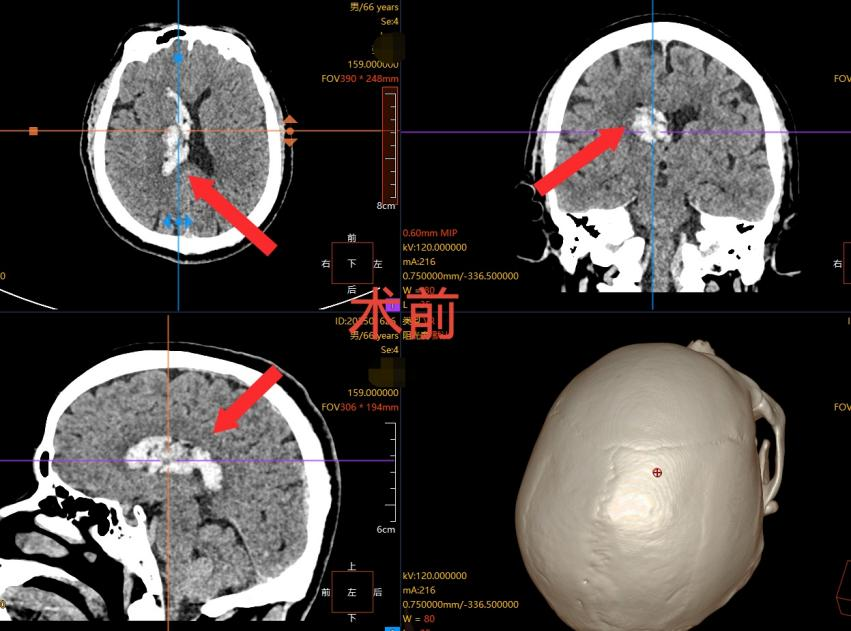

66 岁的张先生在家中突发剧烈头痛,伴随频繁呕吐,家人察觉情况危急,立即将其送往我院就诊。经头部 CT 检查,张先生被确诊为 “右侧丘脑出血并破入脑室系统”—— 这是脑血管疾病中极具风险的类型。

丘脑位于大脑深部,是重要的神经功能中枢,一旦出血破入脑室,极易堵塞脑脊液循环通路,导致颅内压骤升,进而引发脑疝,甚至危及生命。更具挑战的是,传统开颅手术创伤大、风险高,对于高龄患者而言更甚。

(箭头处白色信号为脑出血形成的血肿)